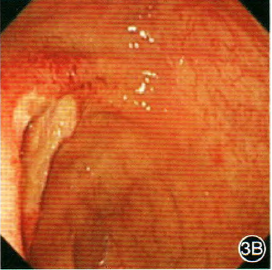

内镜下这些特征可能是艾滋病特征性表现